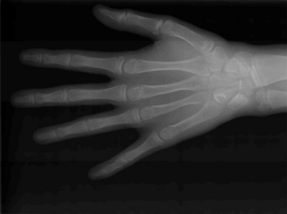

Рентген кисті

400 грн